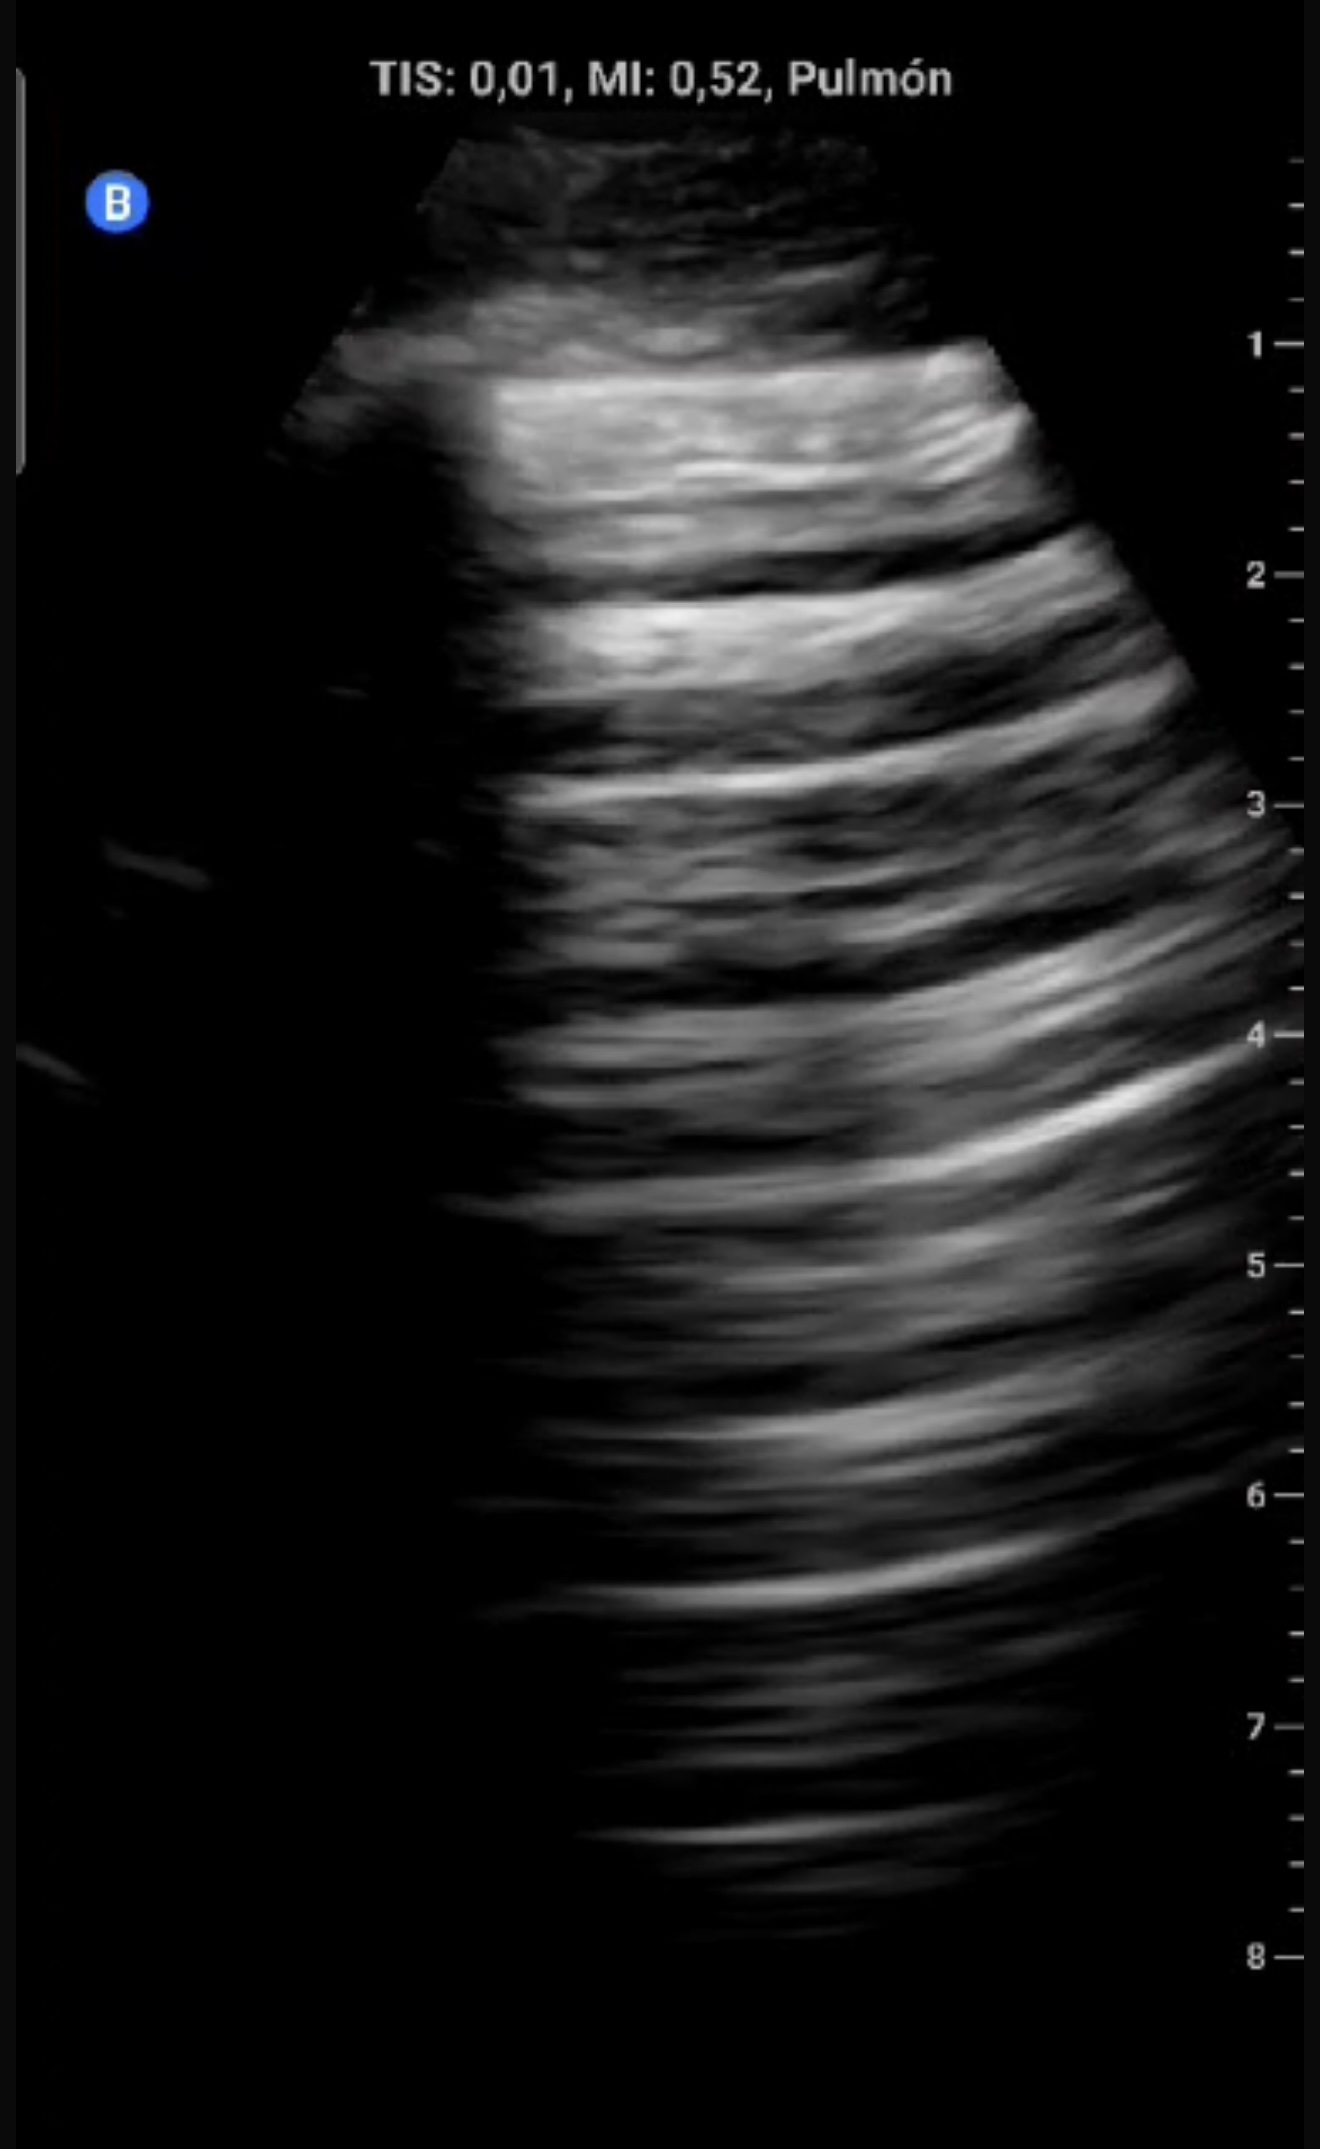

Eco clínica:

Ausencia de deslizamiento pleural (línea pleural fija), sugiriendo neumotórax.

Descripción de los hallazgos ecográficos

En modo B, ausencia de deslizamiento pleural con línea pleural estática hiperecoica. En modo M, signo de code bar (ausencia del signo de la playa).